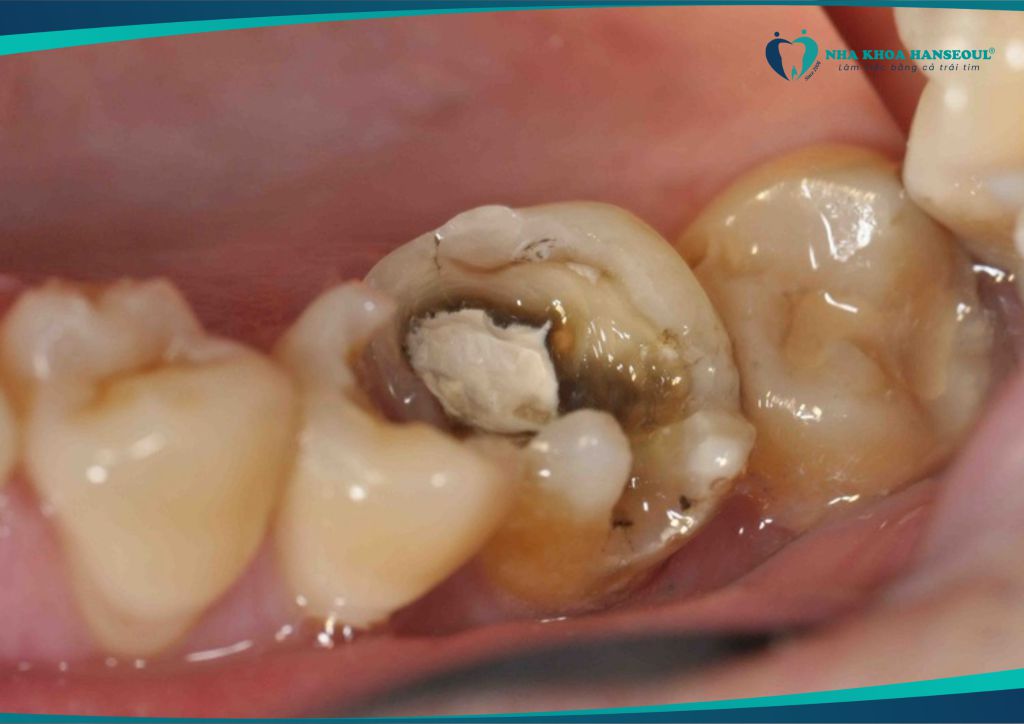

2.1 Gây sâu răng số 7 – răng hàm quan trọng

Răng số 8 mọc lệch thường đâm vào răng số 7, tạo thành khe hẹp khó vệ sinh. → Thức ăn mắc lại lâu ngày dẫn đến sâu răng số 7, viêm tủy, thậm chí mất răng vĩnh viễn.

“Răng khôn mọc ngầm trong xương hàm gây ra tình trạng dắt thức ăn, dẫn đến hôi miệng. Nặng hơn có thể gây tình trạng viêm quanh thân răng 8, sâu răng 8 và răng số 7 có chức năng ăn nhai. Nặng hơn nữa là gây ra áp xe quanh thân răng 8. Vì vậy, răng khôn thường có chỉ định nhổ ngay cả khi nó mọc thẳng.” – Bác sĩ Thắng (Khoa Tiểu phẫu Răng Miệng – Nha khoa Hanseoul)

Răng số 8 không phải lúc nào cũng cần nhổ. Nhưng nếu mọc lệch, mọc ngầm hoặc gây đau – bạn cần xử lý càng sớm càng tốt để tránh các biến chứng nguy hiểm. Ví dụ như sâu răng số 7, viêm nướu, nhiễm trùng hoặc ảnh hưởng dây thần kinh.